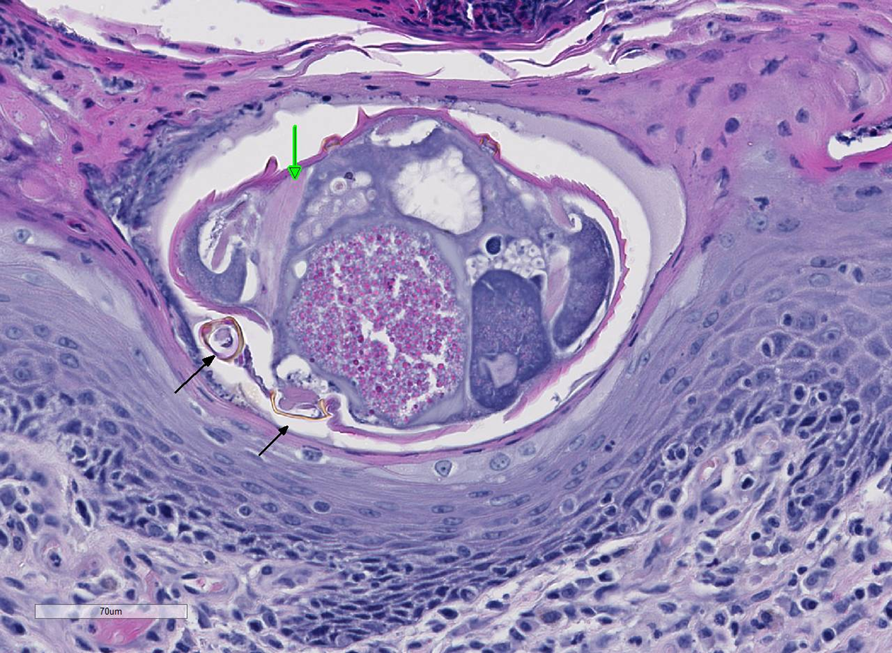

How does demodectic mange present histologically?

Intrafollicular mites with characteristic cigar shape

Perifollicular mixed dermatitis

Possible furuncolusis

Abscess formation due to bacterial breech